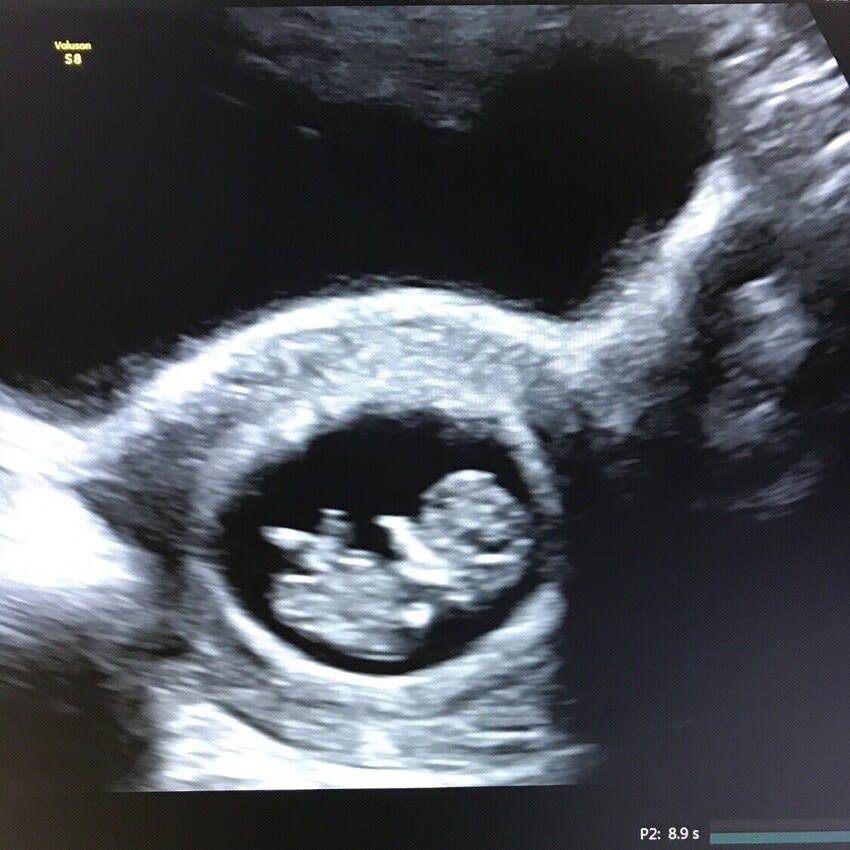

Early Pregnancy Dating Scan

FROM 7-15 WEEKS

✓ 2D Dating Baby Scan (Normally £90)

✓ Confirms Single or Multiple Pregnancy

✓ Calculates Estimated Due Date (EDD)

✓ Visualise Heartbeat & Heart Rate